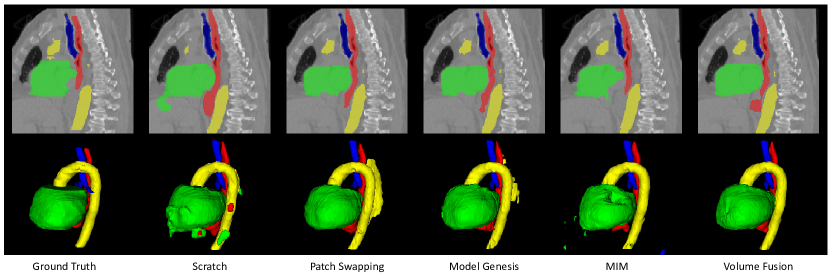

In this experiment, we used PData-1K to pretrain 3D UNet [1] with these different SSL methods respectively, and applied the pretrained models to the SegTHOR dataset. The quantitative evaluation results are shown in Table 2. Compared with learning from scratch, Patch Swapping [5], Model Genesis [52] and MIM [8] improved the average Dice from 84.92% to 86.18%, 86.81% and 86.97%, respectively, and reduced the average ASSD value from 3.17 mm to 2.78 mm, 2.71 mm and 3.03 mm, respectively. Our proposed Volume Fusion outperformed these three methods, with an average Dice and ASSD of 88.30% and 1.78 mm, respectively. Fig. 6 shows a visual comparison between these methods. It can be observed that learning from scratch had an over-segmentation of the heart and esophagus, with an under-segmentation of the aorta. Patch Swapping [5] and Model Genesis [52] obtained an over-segmentation of the aorta, while MIM [8] obtained a poor segmentation of the heart. In contrast, Volume Fusion obtained smoother results with less mis-segmentation than the other methods.